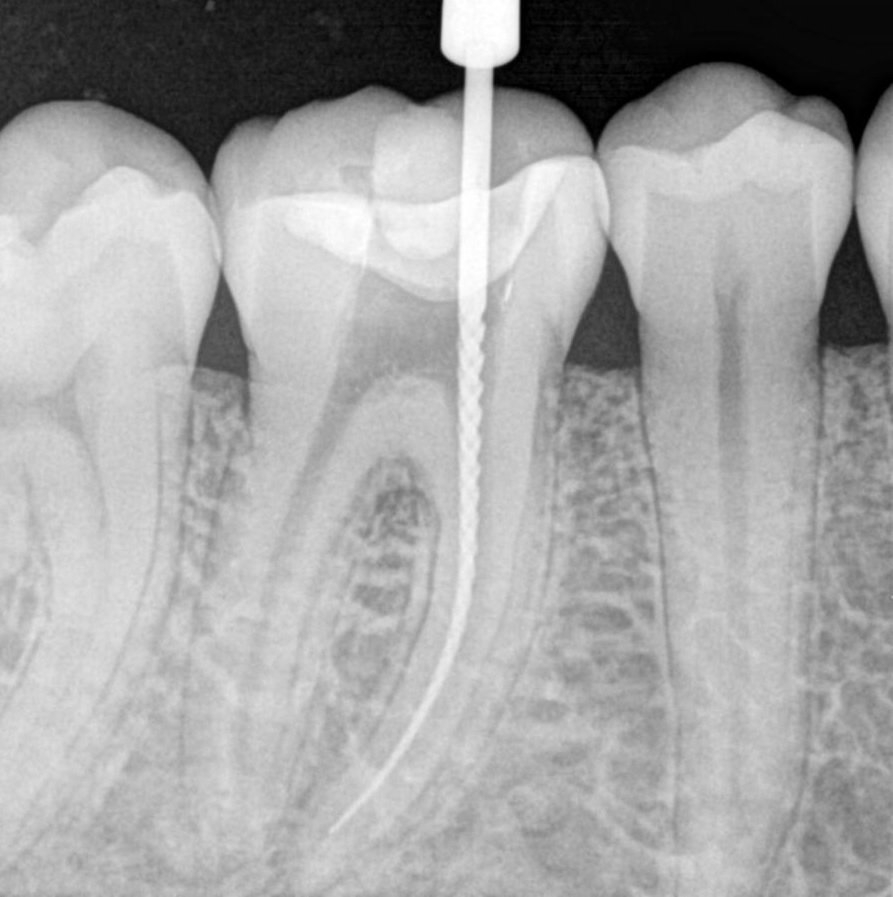

From endodontics.styleitaliano.org

Management of broken files A clinical approach Style Italiano Endo X Ray Tips Basic tips for root canal xrays. Dental radiography allows for the identification of pathologic. Whatever the purpose of the radiograph, the aim is to get consistently high quality images, with the minimum radiation dose, and nowhere is that more important than in endodontics. Endodontics aims to prevent or eliminate apical periodontitis. Discuss reasons for limiting the number of exposures. Describe. Endo X Ray Tips.